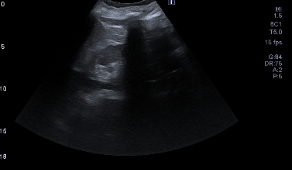

Ecografía abdominal:

Hígado y bazo normales, vesícula alitiásica, riñones normales. Páncreas con porción cefálica engrosada, contornos irregulares y ecogenicidad heterogénea, con áreas hipodensas sugestivas de edema y leve líquido peripancreático. No hay líquido libre intraperitoneal significativo.